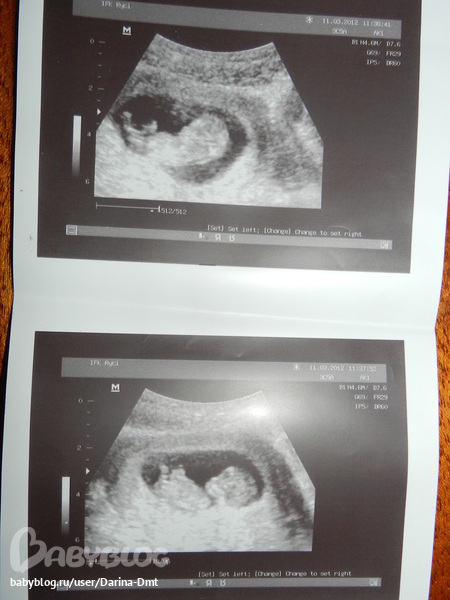

вчера делали узи...после очереди в 2 часа ,я таки добралась до узиста,все посмотрели,послушали сердечко....мы уже большие совсем ктр 43мм,чсс 165у/м

ерзали там,вертелись,все что надо все показали....и еще нам сказли что мы скорее всего девочка

,вот такие мы счастливые)сегодня сдали все анализы...результаты узнаем 28....и вот наше фото)